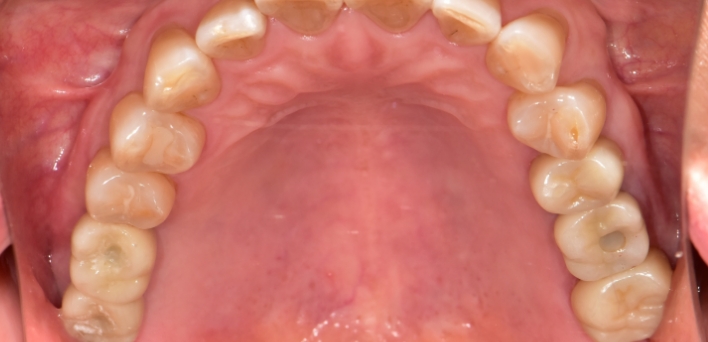

임플란트 : 손 ** 님 (50대)

After After

2020.02.30

※ 더서울치과의원은 의료법을 준수하며 위 케이스는 실제 환자의 동의를 얻은 사례로 치료 전, 후가 동일한 환경에서 촬영되었습니다.

환자 케이스에 따라 부작용이 발생할 수 있습니다. 이 부분은 의료진의 충분한 상담과 체크를 통해 예방하고 줄일 수 있습니다.

[임플란트 부작용] 수술 후 관리가 소홀할 경우 출혈, 주위염 등의 부작용이 발생할 수 있어 구강 위생을 철저히 유지하고, 정기적인 검진을 통해 상태를 점검하는 것이 중요합니다.

위, 아래 6개씩 식립

디지털 풀아치 임플란트

임플란트 Before & After